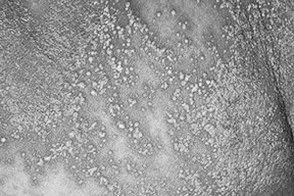

Ексудативний або пустульозний псоріаз у дітей